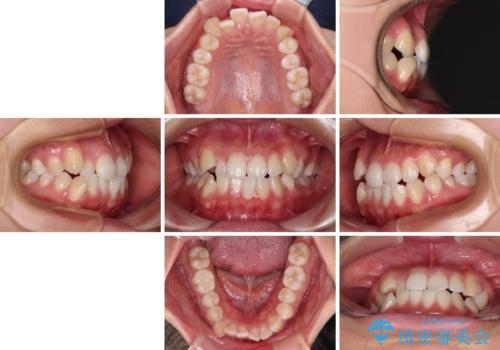

- 前歯のデコボコを治したいとのことで来院された患者様です。

インビザラインによるマウスピース矯正も適用となる歯列でしたが、できる限り楽して、短期間で治したいとのことで、ワイヤー装置にて矯正治療を行うこととしました。